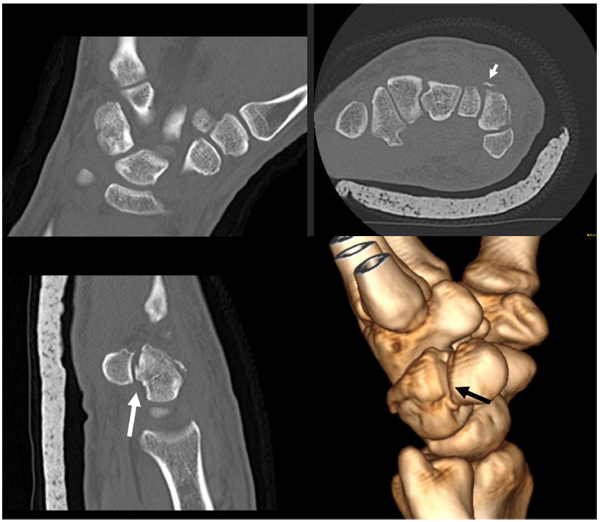

From benthamopen.com

Intraarticular Fracture of the Distal part of the Triquetrum within Triquetrum Fracture X Ray Triquetral fracture is carpal bone fracture that generally occurs on the dorsal surface of the triquetrum. It may be fractured by means of. A triquetrum with a normal appearance. Triquetrum fractures are common carpal fractures that are often associated with other injuries to the wrist. Triquetral fractures are the most common carpal fracture after scaphoid fractures. Diagnosis is confirmed with. Triquetrum Fracture X Ray.